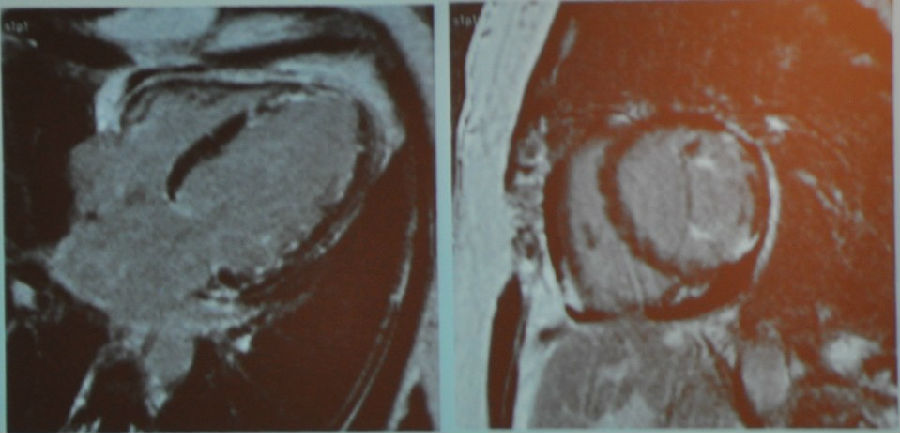

图2 MR电影成像

室间隔壁变薄,心尖部收缩功能不全,短轴观示前壁收缩功能不全。心尖部有异物。

图3 MR增强成像(从左到右依次为三腔心切面、四腔心切面、短轴切面)

从MR增强成像中可以看到,心脏上黑色的部分是正常心肌,而白色的部分为瘢痕组织。该图显示了心肌梗死的典型表现。通过增强我们可以看到心尖部的异物是一个血栓,这个在一般的心脏超声上是难以发现的,因为它非常小。我们还可以看到,实际上患者心梗的面积要比上面短轴观所示前壁收缩功能不全的程度严重得多。